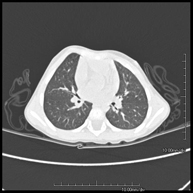

- High resolution Chest CT

Diagnostic test to examine the lung using CT (Computed Tomography) equipment to obtain two- and three-dimensional images, that allow a highly specific anatomical examination of the lung, being able to assess very small anatomical structures. This technique is very important among patients with suspected lung disease.